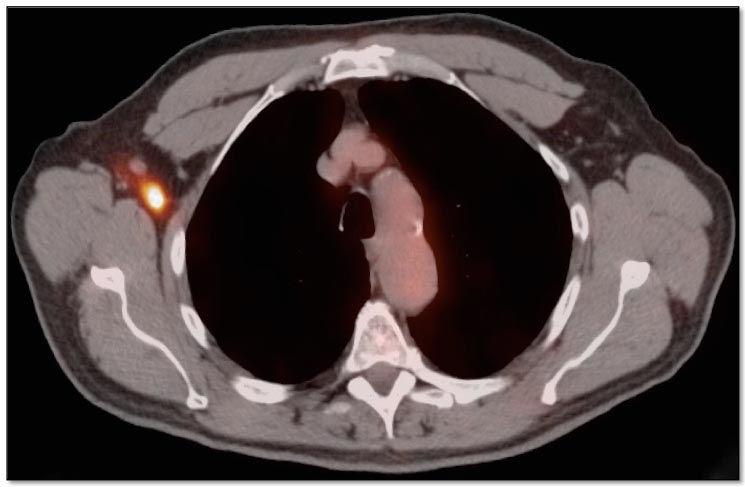

Extravasation:

FDG is injected intravenously. As many oncology patients have challenging venous access, partial extravasation of FDG during injection is not uncommon.

This extravasated FDG can cause false positive uptake in adjacent nodes and vessels (discussed here). Additionally, the resulting decrease in available FDG for circulation in the body (and absorption into tumors) can lead to false negative results (the “Sponge Effect”, discussed here). [FIG. 5] [FIG. 6]